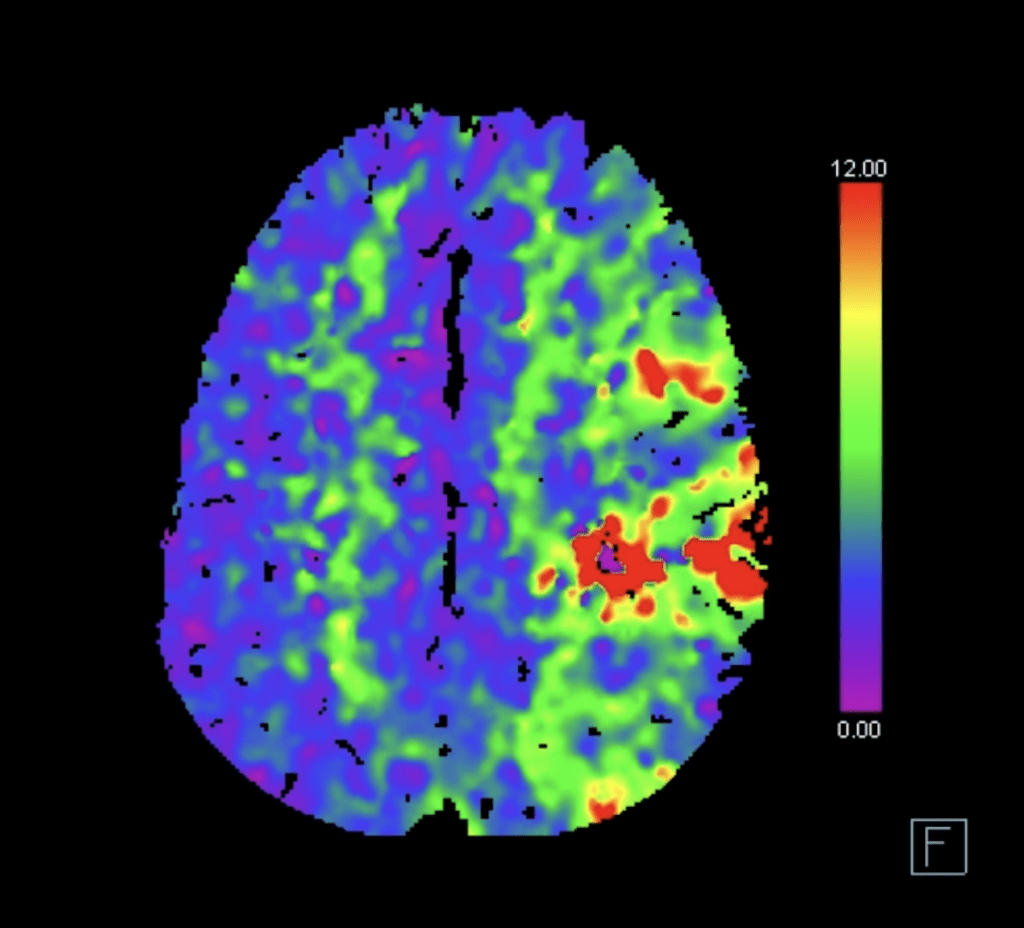

Vengono eseguiti una TAC cerebrale, un angiogramma e una scansione della perfusione cerebrale.

Interpretazione della TAC